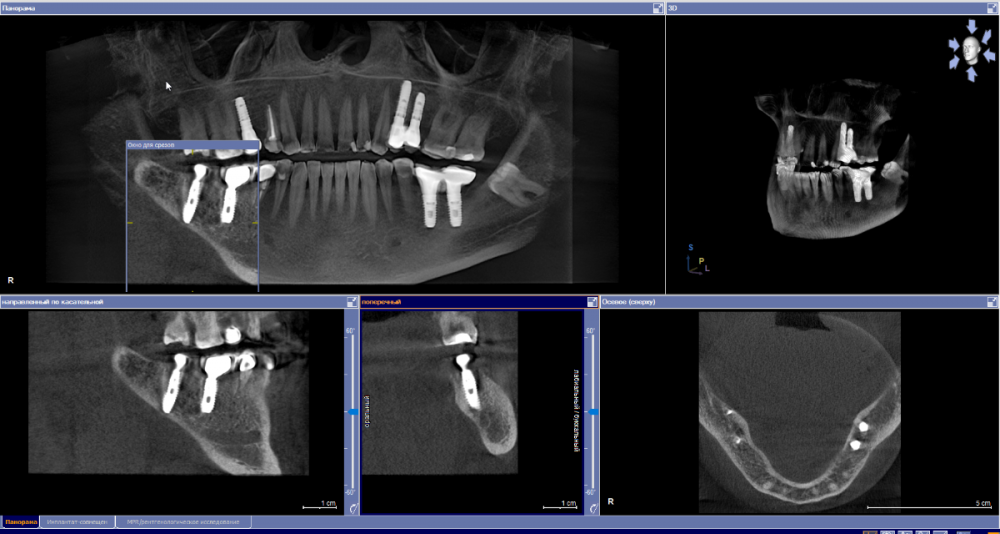

se77777 Опубликовано 19 сентября, 2022 Поделиться Опубликовано 19 сентября, 2022 Добрый день, 37. Эндодонтическое лечение с микроскопом 2,5 года назад. Слабая невнятная боль возвращалась от случая к случаю. Даже была тенденция к затягиванию полости. Но, похоже, не получилось. После коронавируса и серьезной нагрузки, впервые боль на короткое время обострилась. Полость, похоже, растет. От дна полости кисты до канала нерва 6 с небольшим мм. Показано ли в таком случае одномоментное удаление и имплантация? Спасибо. Ссылка на комментарий

red_butler Опубликовано 19 сентября, 2022 Поделиться Опубликовано 19 сентября, 2022 3 часа назад, se77777 сказал: Показано ли в таком случае одномоментное удаление и имплантация? Срезы не совсем корректные, но одномоментная имплантация скорее всего возможна 1 1 Ссылка на комментарий